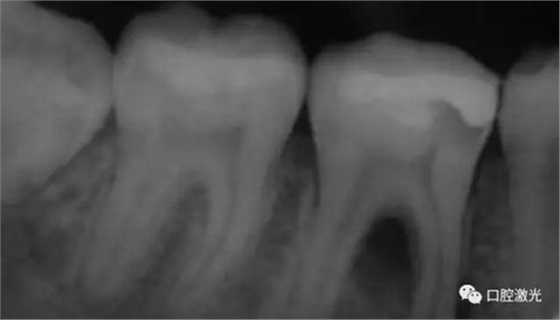

46治療前X光片

半導(dǎo)體激光治療中

6個(gè)月后治療效果